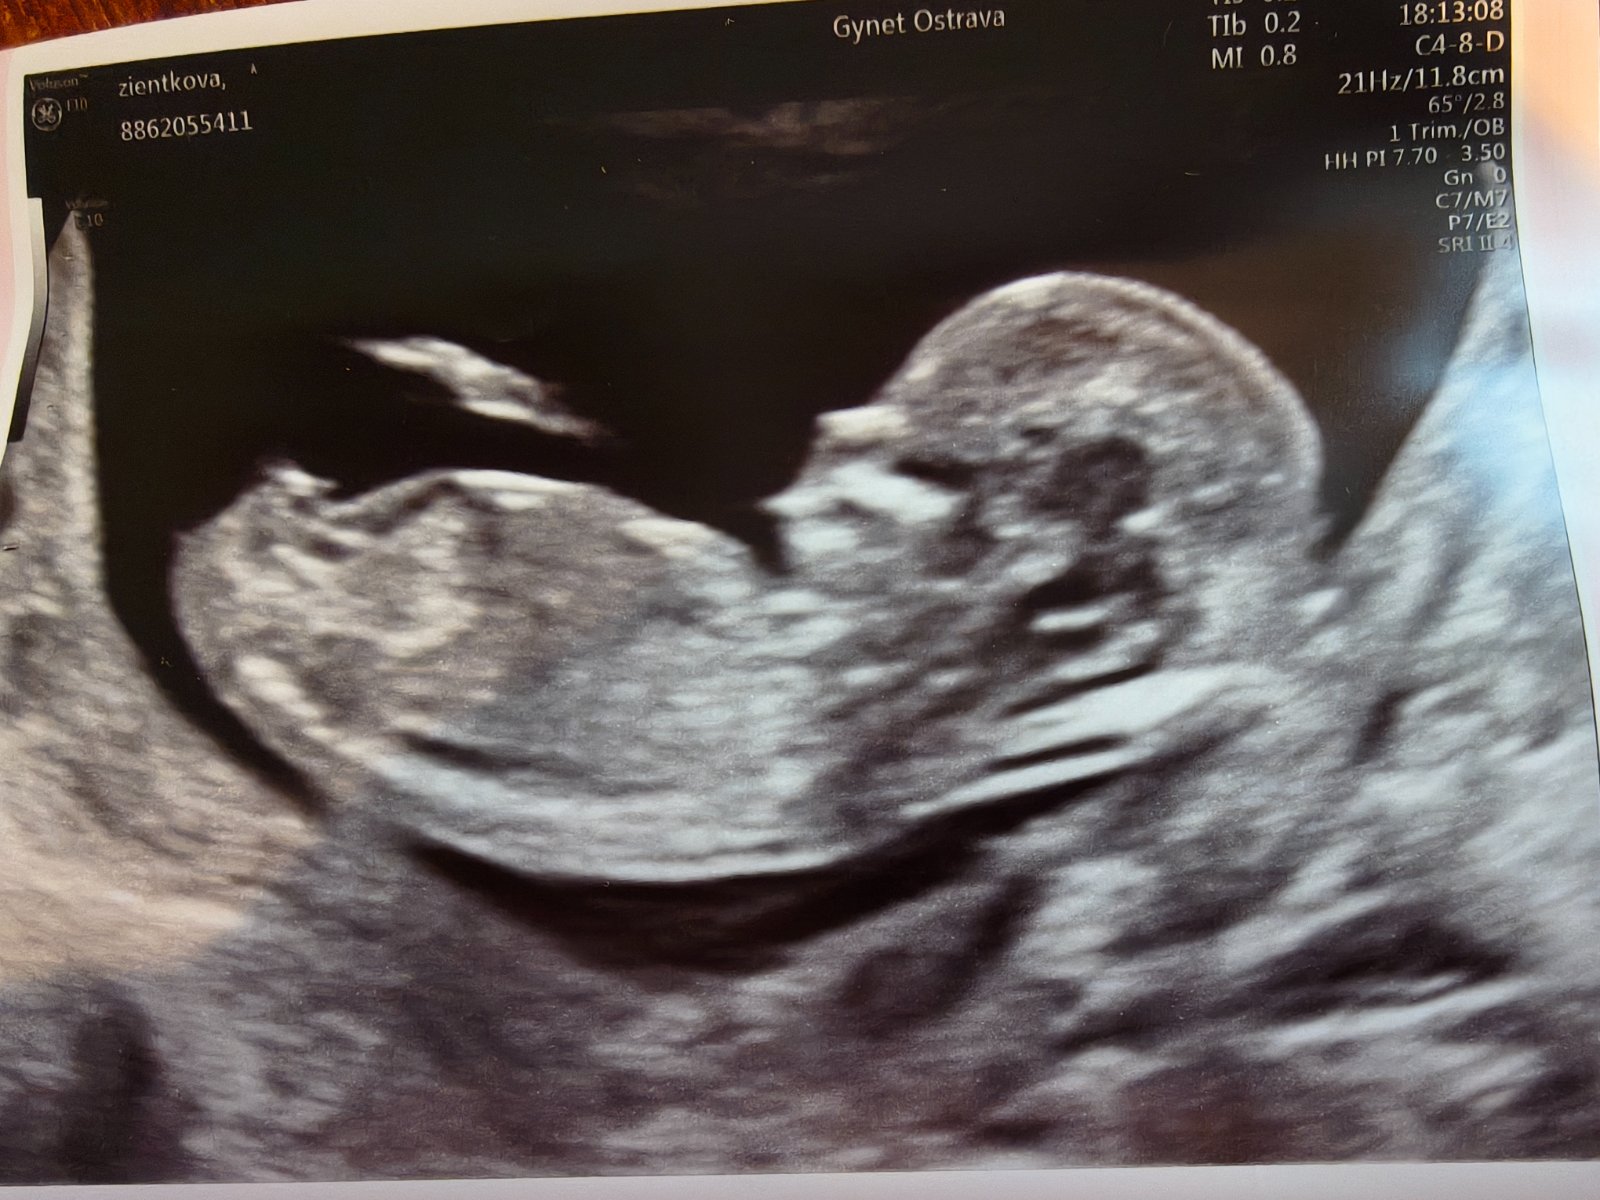

Ahojky pochlubte se svými fotografiemi z 1 screeningu? Ráda se podívám dozvěděli ste se už co čekáte?

@lujhu já byla teď ve čtvrtek a prý na 99,9% holka 🤣 když jsem se doktora ptala, jestli je to poznat podle toho "hrbolku" či jak to poznávají, tak na to místo najel a říkal, že tam není o čem polemizovat. Byl rovný, jak přímka 🤣

@lujhu jestli narazis na tvoji fotku, tipuji holcicku, moje mala ve 13+2tt a na 90% holcicka